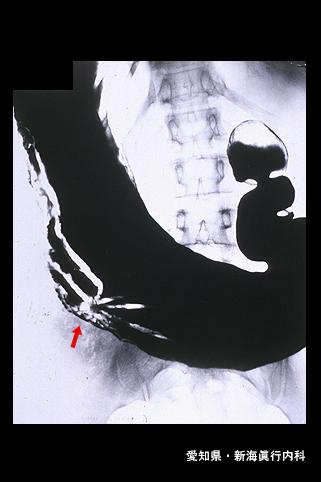

疾病(病理主体)的分类恶性上皮性肿瘤/印戒细胞癌

部位(按器官分)胃(部位)/体部

检查方法X线

肿瘤的肉眼分类0型(表在型)/IIc型(IIc+III)

肿瘤最大直径30~34

肿瘤的深度m